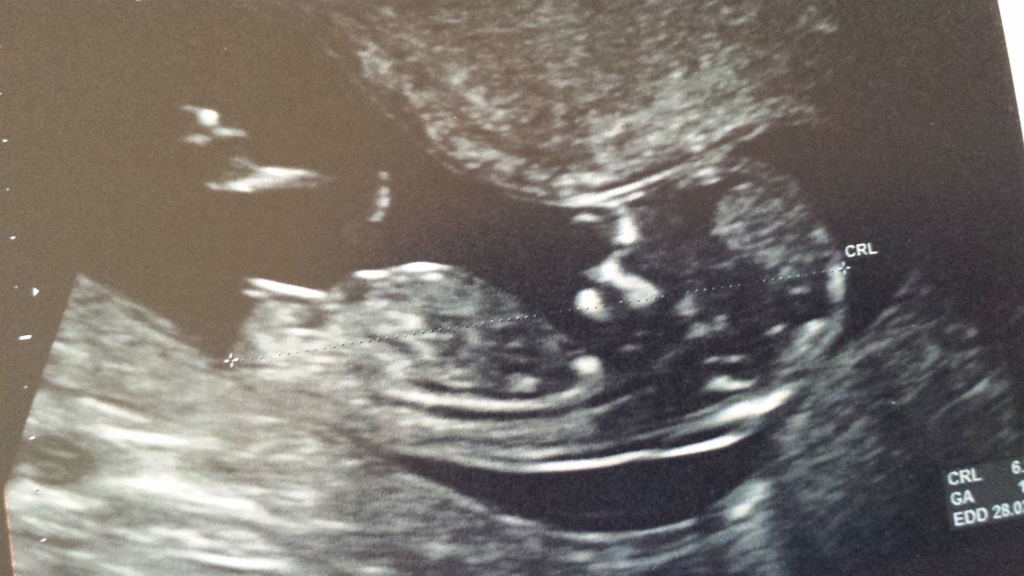

Please guess my nub!! :-)

Attachment 13281Attachment 13282